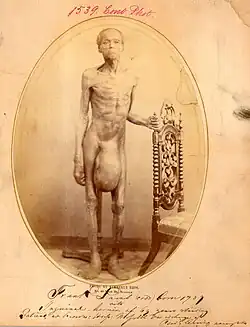

(photo: United States Military Medical Archives)

The photograph is blurry as the patient was shaking too much.